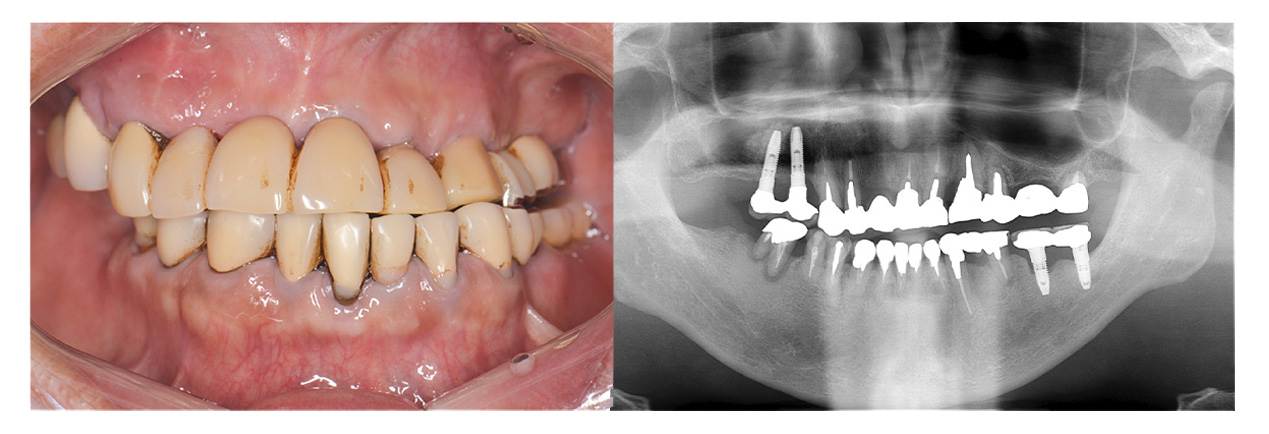

症例写真の紹介

ここで、当院がこれまでに治療してきたオールオン4やザイゴマの症例写真をご覧ください。お口の状況がどれほど改善されるかがイメージしやすくなるかと思います。

症例③オールオン4 + ザイゴマ

• Before

• After

合わない総入れ歯と歯周病がひどい部分を全部除去してオールオン4とザイゴマにて治療した症例。